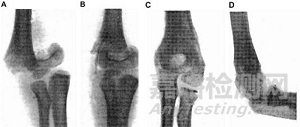

早在1907年,Lambotte就使用鐵絲環(huán)扎術和一塊帶有六個鋼螺絲的鎂板來固定骨折的小腿,但是由于鎂和鐵接觸后發(fā)生電化學反應,加速了鎂的腐蝕,術后一天即觀察到了大量的皮下氣腔,并伴有局部有腫脹和疼痛。因此在排除了鎂和其他金屬混用后,Lambotte與其助手Jean Verbrugge用鎂釘治愈了4例兒童肱骨髁骨折(圖1),除發(fā)現(xiàn)氣泡產(chǎn)生外,沒有其它不良反應發(fā)生。Jean Verbrugge在接下來的幾年里,采用鎂及其合金(AZ63和Mg-8wt.%Al)進行了25例骨折治療的臨床實驗,如圖2所示。由于鎂在植入后的快速腐蝕降解,鎂板和鎂釘固定系統(tǒng)植入三周后,骨折線即消失不見。除此之外,有病人反映,植入部位會有暫時的麻木感覺,但沒有組織感染跡象或不良反應發(fā)生。在這些病例中,因植入尺寸以及位置不同,鎂在人體內在三個星期到一年最終吸收。McBride進行的臨床應用探索,如圖3所示,發(fā)現(xiàn)鎂可以加速治療初期結締組織的早期增殖和愈合組織的增生。1940年,Maier使用了由梭形鎂片制成的針治療肱骨骨折,并且在接下來的14年獲得良好的恢復。

圖1 Lambotte報道的兒童肱骨髁上骨折(A)采用鎂金屬釘固定(B)的病例。幾個月之后,鎂釘全部降解,骨折部位已經(jīng)愈合穩(wěn)定,如圖C所示。沒有感染和疼痛現(xiàn)象發(fā)生,該兒童肘部功能恢復良好(D)。